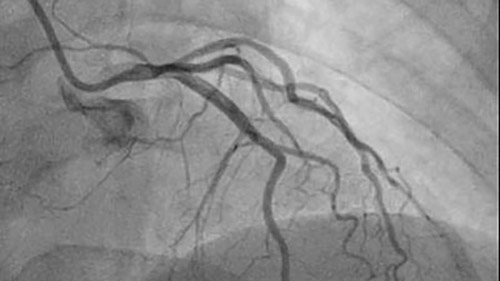

Dynamic Coronary Roadmap creates a dynamic, motion-compensated, real-time view of the coronary arteries. The software program overlays a highlighted coronary angiogram on a 2D fluoroscopic image, creating a colored map that adjusts automatically, providing continuous and exact visual feedback on positioning of wires and catheters.